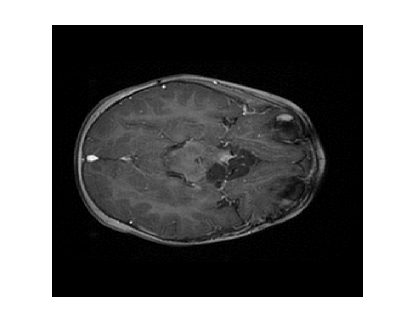

Figure 2: Image reconstruction from Case 20 (a, b, and c) and Case 3 (e, f, and g) of a brain image. Case 20 is the best performing algorithm that uses L1-W and case 3 is the best performing algorithm that uses LACS-MRI

The phantom image that we used in the previous experiment is flat and has less texture while the brain images has a lot of wrinkles and complex shapes. While the phantom image is small, the brain image is too large to calculate fNDsubscript𝑓𝑁𝐷f_{ND} efficiently. Thus, we conducted an experiment in the same setting as the phantom image excluding cases using fAsubscript𝑓𝐴f_{A}: cases 6 through 8 and 14 through 16. In this experiment, contrary to results for the phantom image experiment, L1-W performs better than LACS-MRI. For example, Case 3 performed the best among cases using LACS-MRI but it performs worse than 6 cases that use L1-W. Interestingly, one of the cases that shows an outstanding image recovery purely uses fVDSsubscript𝑓𝑉𝐷𝑆f_{VDS} with L1-W. However, purely using fVDsubscript𝑓𝑉𝐷f_{VD} with L1-W shows a dramatically worse performance. In conclusion, we are unsure why each combination of mixed PDFs and reconstruction algorithm perform differently based on the images processed, but this differing behavior is crucial to highlight for practical applications. We conjecture that the texture of the image is one factor that decides the performance of each algorithm. In the future, we may explore this conjecture and analyze why this happens.